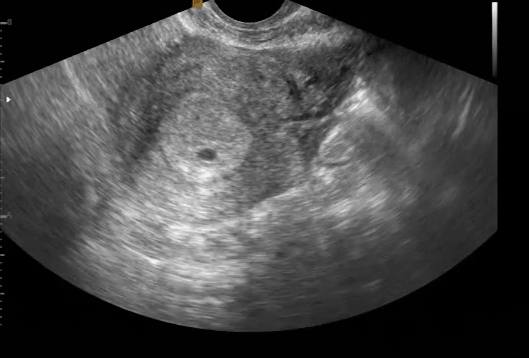

첫 번째 별이 찾아왔을 때는 예민하지 못해서 첫 방문에 심장이 뛰는 소리를 들을 수 있었는데, 두 번째 별은 까만 방안에 ( 선생님이 여기 있다고 알려주었지만 어딘지 모르겠는 ) 존재하는 하나의 점, 아직 심장조차 뛰지 않는 작은 존재였다. 신기하기도 하고 조심스럽기도 하고 복잡한 마음이었다.

초기라 일주일에 한 번 산부인과를 방문해야 했고, 첫 방문 이후 2번 더 산부인과를 방문해서야 두 번째 별의 심장소리를 들을 수 있었다. 심장이 뛰는 소리를 듣기까지 얼마나 조마조마하고 혹시나 잘못되는 건 아닐까 걱정이 많았다. 여자는 이미 노산에 속하는 나이였고, 1호 별은 여자의 뱃속에 동생이 있는 걸 알았는지 여자의 품에 더 많이 안기고 싶어 했기에...

태아의 심장이 뛰는 소리를 듣는 것... 두 번째는 같으면서도 다른 경험이었다.